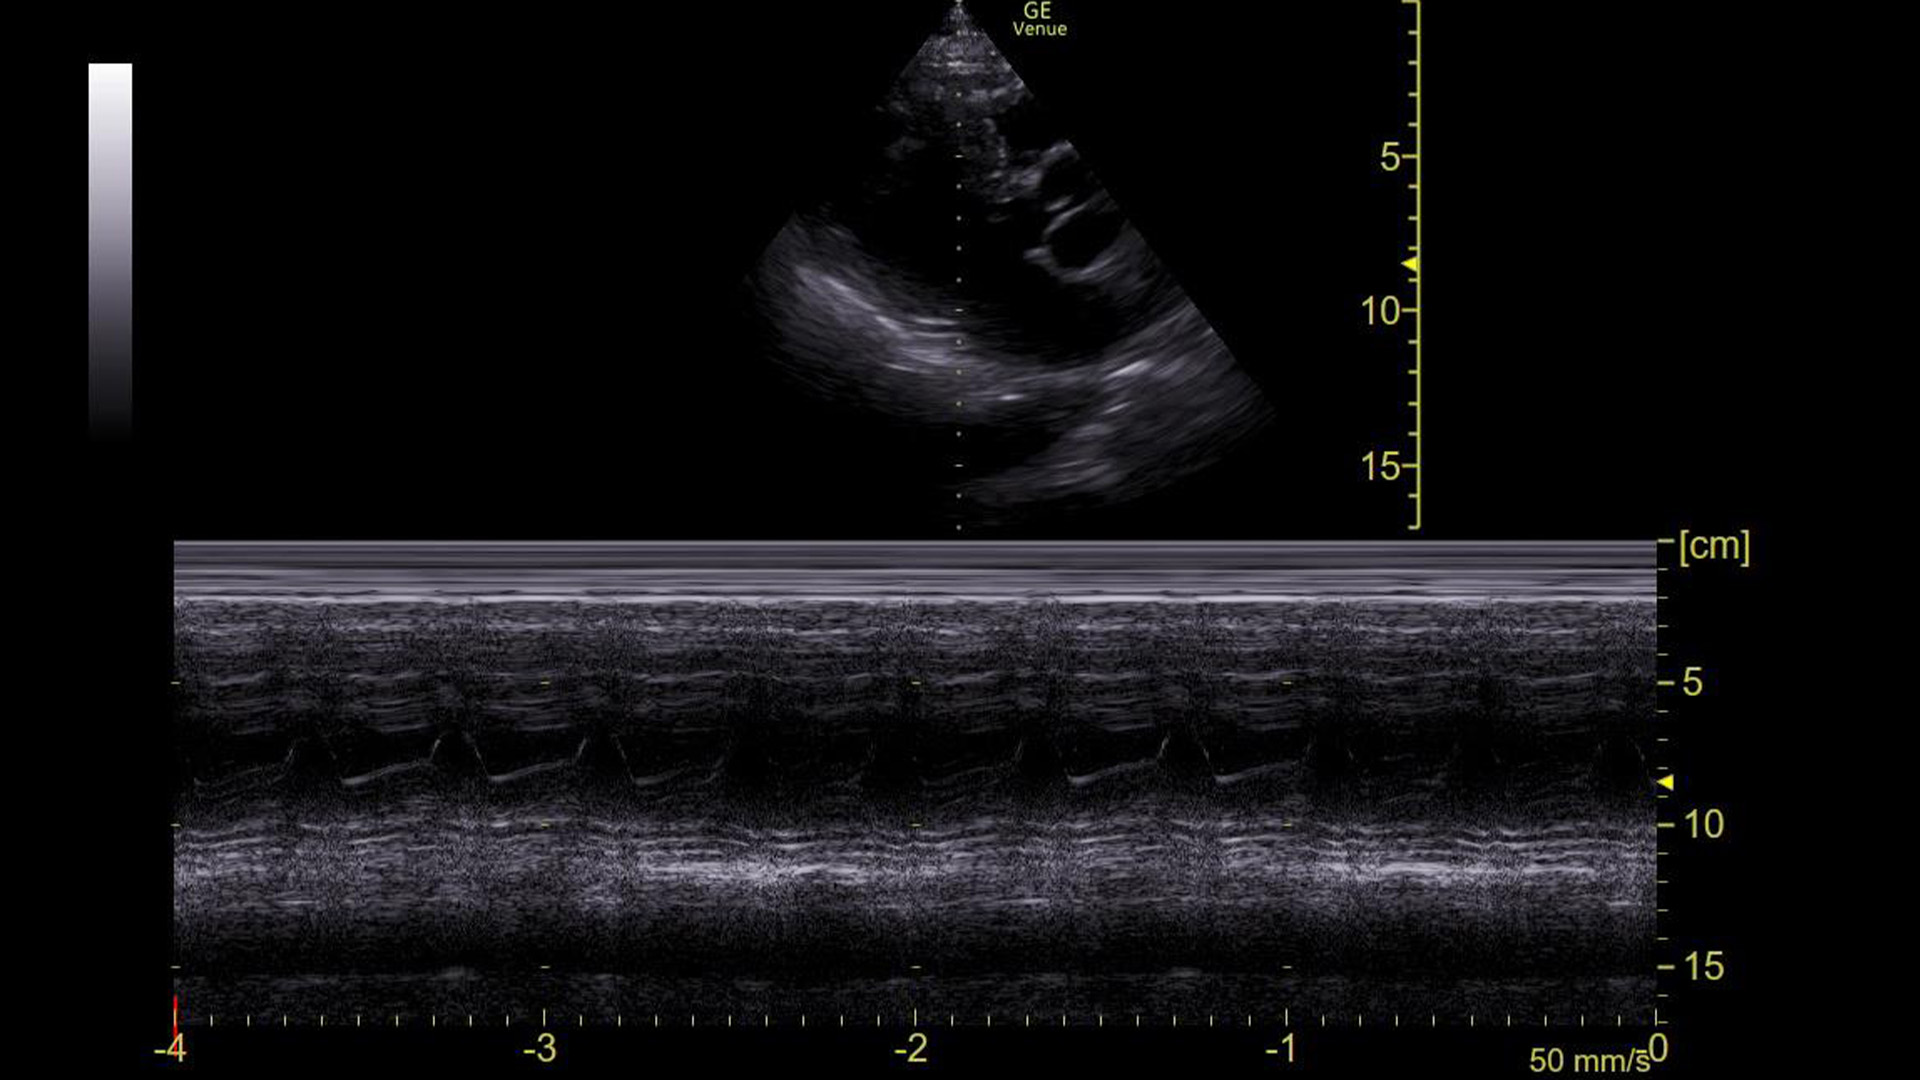

The machine read the ECG as sinus tachycardia, but I had my doubts. So, we obtained this M-mode tracing with the spike over the mitral valve in a parasternal long axis view.

This made it clear that he was in an arrhythmia. The rate was 153, so we assumed it is atrial flutter with 2:1 conduction, but just based on this image and the narrow QRS complex on the ECG, it could have been SVT or a strangely regular atrial fibrillation.

Turn on M-mode and put the spike through the tips of the mitral valve

In a sinus rhythm, we see E-waves and A-waves. This is a normal appearing tracing.

M-mode

M-mode is a way to represent movement on a still image. To use it, a line (often referred to as a “spike”) is placed on a two-dimensional “B-mode” image. A recording is then made of the piece of the image under that spike over time. If nothing moved during the recording, it would produce a uniform/still tracing. However, if there is movement under the spike, it is visible on the tracing.